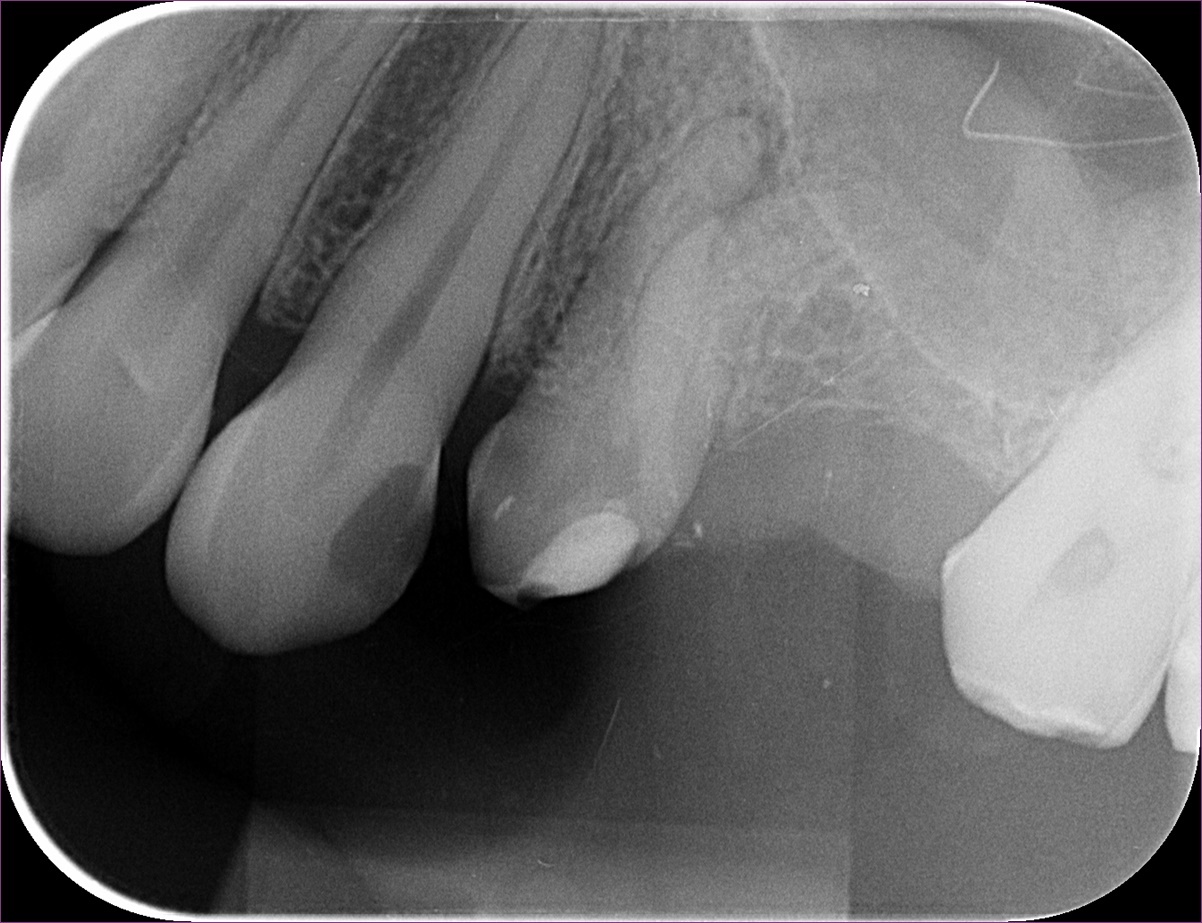

Sajnos a csiszolást követően a négyes fog egyre érzékenyebb lett, így a gyökérkezelés mellett döntöttek. Ám a csatornák görbeségét látva a kiinduló röntgenfelvételen (lásd fentebb), hagyományos módszerrel a kezelésbe nem mertek belevágni. A megoldás tehát a mikroszkópos gyökérkezelés lett.

A mikroszkópos gyökérkezelés menete szerint haladtunk. A fog kinyitása után a csatornákat a látható görbület miatt óvatosan, különleges technikával dolgoztuk fel. Már a kezelés elején érzékelhető volt, hogy a két, egyébként külön kijárattal rendelkező csatorna között van kapcsolat. Az egyik csatornába egy speciális szívóberendezést helyezve a másik csatornából is sikerült eltüntetni a folyadékot.

Közvetlenül a gyökértömés előtt a majdani gyökértömő „pálcikákkal” készült röntgenfelvételen ellenőriztük, valóban jó helyen vagyunk-e, és az elektromos bemérő készülékünk segítségével jó hosszokat sikerült-e megállapítanunk.

A felvételen egyenesebbnek látszó gyökérben rövidebbnek tűnik a hossz a röntgenen látható véghez képest, azonban itt nem a gyökércsúcson van a kijárat, hanem a gyökér oldalán.

(A szalagszerű képlet a kofferdam-kapocs árnyéka.)